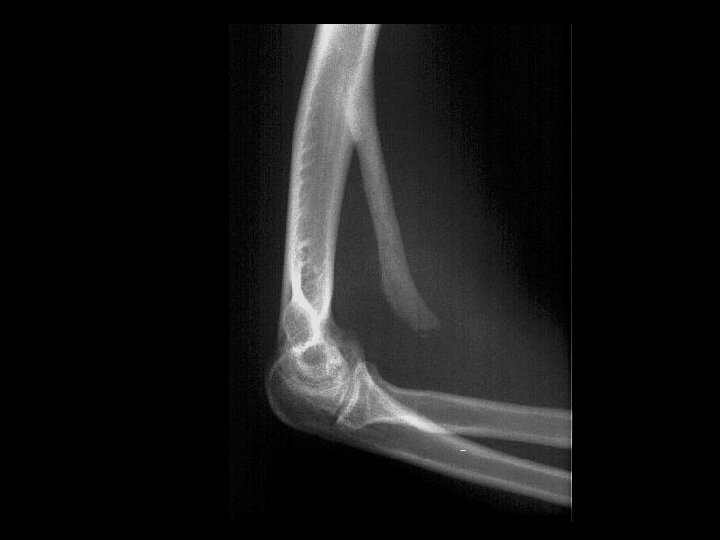

Hypertrophic Osteoarthritis • • Findings: – Diffuse symmetrical periosteal reaction of the distal radius, ulna, and tibia ddx: – Adults • Pulmonary • Pachydermoperiostitis • Vascular insufficiency • Thyroid acropachy • Fluorosis – Peds • Caffey disease • Leukemia • Rickets • Hypervitaminosis A